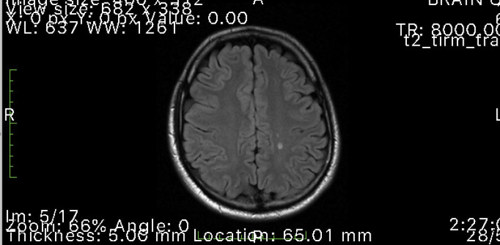

Ironically, the day after writing my neuro-optometry review, Josh sent me his MRI scans. He appeared to have a couple of demyelinating lesions typical of MS, which were confirmed by both the GP and his neurologist. The neurologist then arranged for a lumbar puncture and confirmed the diagnosis of MS, prescribing Josh oral tecfidera capsules, which thankfully for Josh were also covered by Medicare. All this took place before Josh manifested any signs of MS so he is very grateful.

Fig 2. MRI scan showing demyelinating lesions typical of MS